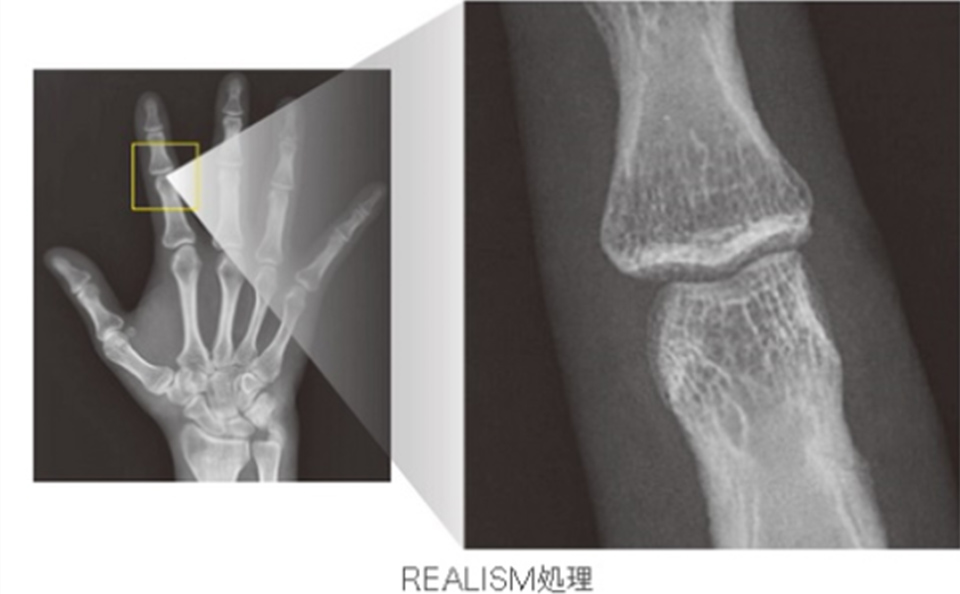

⼀般撮影部⾨

⼀般撮影部⾨は、胸部や腹部、また頭部から四肢などのX線撮影を⾏います。

当センターでは、FPD装置(フラットパネルディテクタ)の採⽤により、全⾯デジタル化が実現されております。

デジタル画像処理技術により、⾼解像度、⾼鮮鋭化の診断画像が提供でき、低被ばくでの撮影が可能となりました。